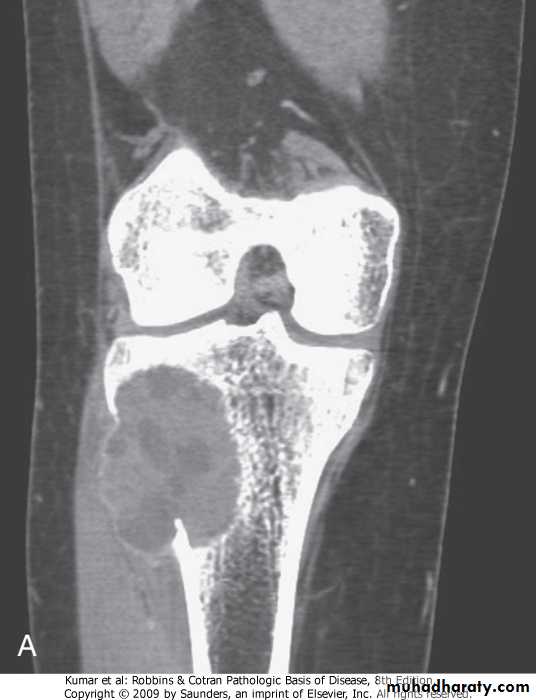

ANURYSMAL BONE CYST:.benign tumor of bone characterized by multiloculated blood-filled cystic spaces.mostly occurs during 1st 2 decades of life, and involves metaphyses of long bones and vertebral bodies.causes pain and swelling, rarely fractures.most lesions are lytic with shell of reactive bone at the periphery

Tibia, aneurysmal bone cyst